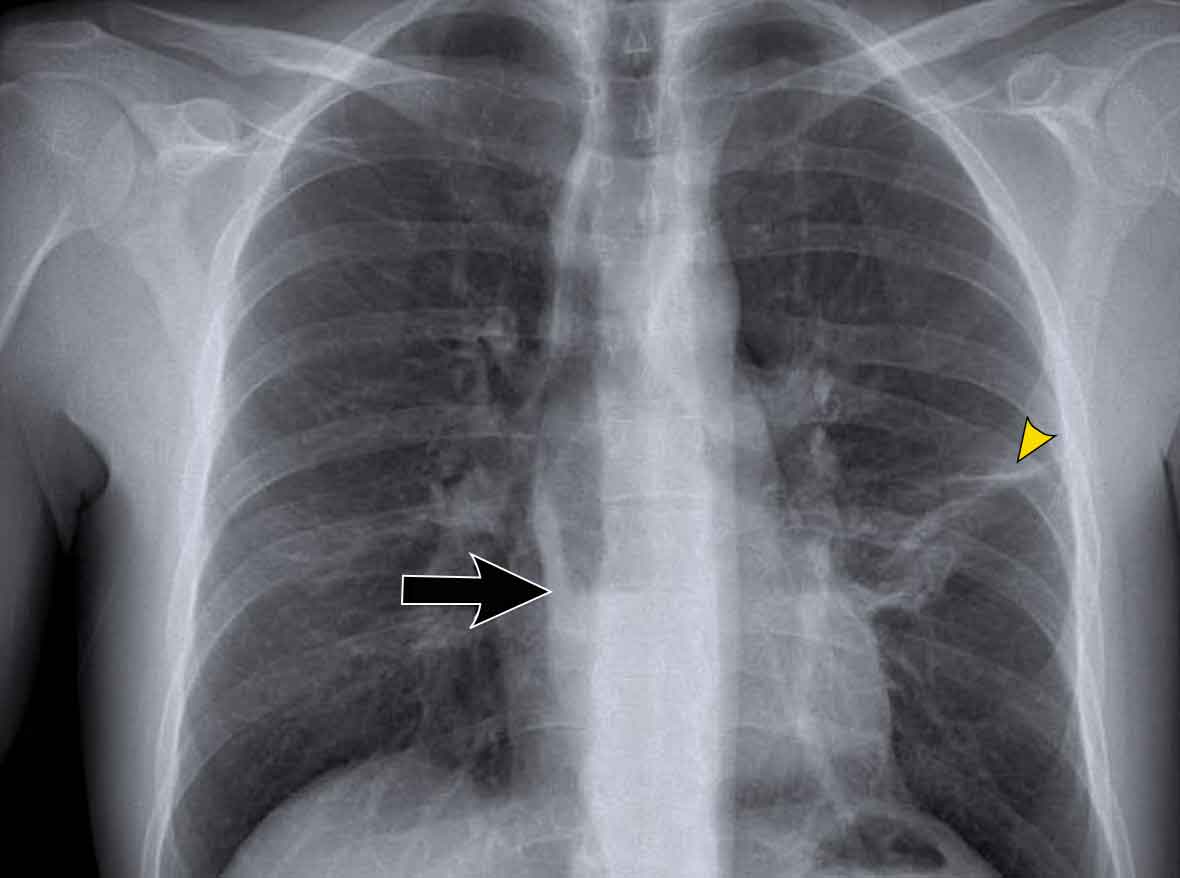

Displacement of the Azygoesophageal Line (2) – Subcarinal Lymphadenopathy

A common cause of displacement of the azygoesophageal line is subcarinal lymphadenopathy (station 7).

On the chest X-ray, note superior displacement of the azygoesophageal line just below the carina, consistent with enlarged subcarinal lymph nodes (black arrow).

Additional right paratracheal lymphadenopathy is seen, displacing the right paratracheal stripe (white arrow) and deviating the trachea to the left.

Continue with PET-CT...

PET Imaging

• PET-CT demonstrates extensive hypermetabolic lymphadenopathy in the mediastinum and neck, which is more conspicuous than on chest radiography.

• Cervical lymph nodes are involved—an important finding as they are accessible for biopsy.